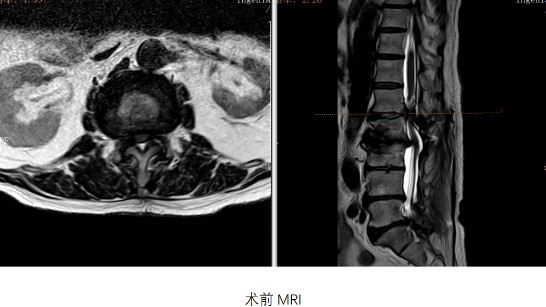

今年年初,童老爺子因鄰椎病再度陷入困境——腰痛、下肢麻木、間歇性跛行讓他寸步難行。于是在家人陪伴下來到寧波市第九醫院脊柱外科。

到門診時,他不僅驚嘆于如今現代化醫院的建設,還感嘆多年來九院骨科與華山醫院的合作更加深入?!霸瓉?個椎間盤所做的工作,現在由4個椎間盤來承擔,這么多年時間負擔下來現在吃不消了。”接診的寧波九院脊柱外科負責人陳曉杰主任醫師發現,問題根源正是20年前手術成功的“代價”:術后應力改變,分散到上下相鄰的椎間盤,加大相鄰節段的運動量和壓力,導致相鄰節段退變、椎管狹窄,這種繼發于手術之后的疾病就被統稱為鄰椎病。

然而,童老爺子的翻修手術面臨三大難關:一是尋找20年前的內固定記錄;二是拆除早已退市的老式器械;三是更換最新內固定的手術難度。